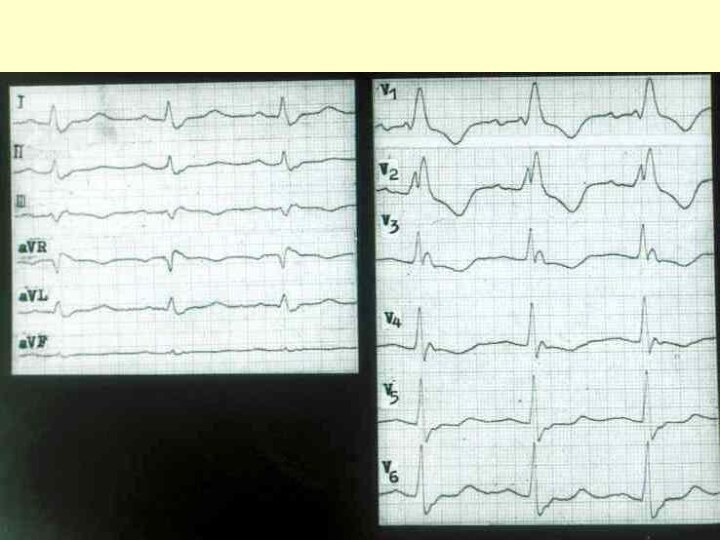

Слайд 52 Блокада левой ножки пучка Гиса

Блокада левой ножки пучка Гиса